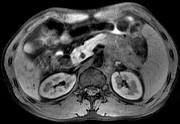

问题 男45岁、腹部胀痛不适、胃纳减退、体重减轻、中腹部可触肿块,影像检查如图,应诊断为 ( )

选项 A.急性胰腺炎 B.慢性胰腺炎 C.胰腺体尾部癌 D.胰岛细胞瘤 E.腹膜后淋巴结结核

答案 C